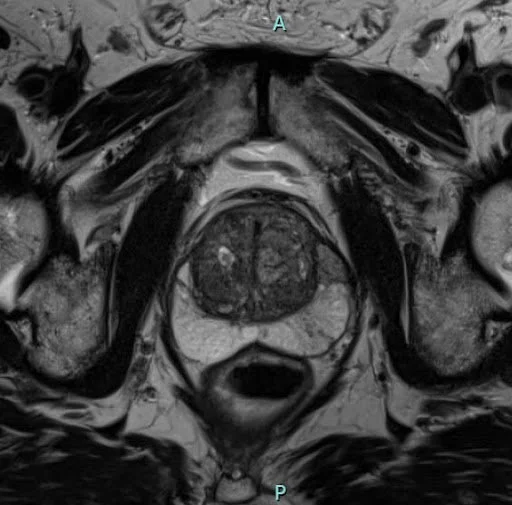

Мрт при раке простаты